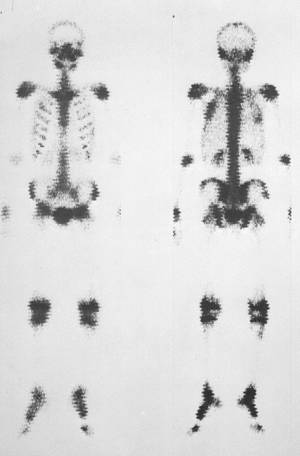

‘½”­«ŠOœŽî

99mTc ‚P‚Tmci

ƒXƒLƒƒƒ“ƒXƒs[ƒh F‚R‚O‚O‚ƒ‚^‚‚‰‚Ž

”xŠà

67‚f‚ ‚Qmci